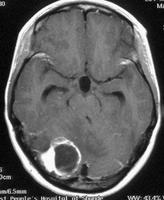

血管母細胞瘤可以用注射顯影劑的電腦斷層或是核磁共振掃描來加以診斷。在這些檢查中,注射顯影劑之後,血管母細胞瘤會在腦或是脊髓中顯現出亮白色的病灶。血管母細胞瘤往往會跟一些腫瘤很像,例如腦膜瘤、轉移性腦瘤或是一些血管病變,例如動靜脈畸形。

放射線手術治療腫瘤,例如血管母細胞瘤,通常是在門診中進行的。因此病患在治療中並沒有什麼太大的感覺。在放射線手術治療後,病患會定期以腦部或脊髓的掃描來做追蹤。大多數的放射線手術治療中心會在術後第六個月,以核磁共振掃描來做追蹤,以監測腫瘤縮減的程度和查看腫瘤周圍腦組織是否有出現放射線治療的副作用。